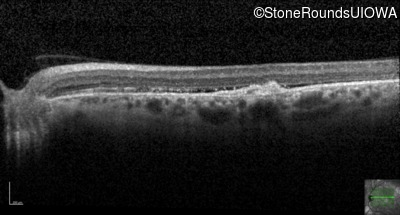

Optical Coherence Tomography - Right - 20/80

Exemplar / OCT Stack

OCT Stack